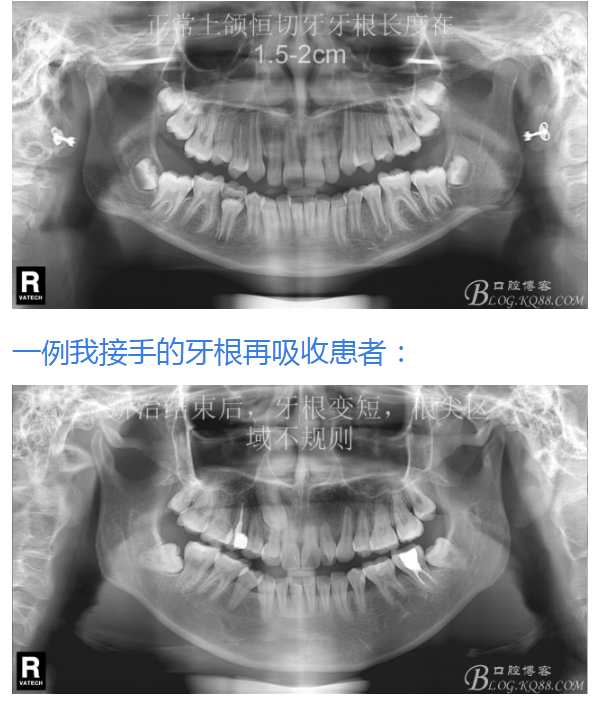

鐘佳溪:正畸治療不可忽視的副作用——牙根再吸收

對牙根再吸收的研究持續(xù)了一個(gè)多世紀(jì)。 一般被認(rèn)為是正畸治療的一個(gè)不可避免的副作用。當(dāng)正畸力中斷或減低到某個(gè)水平以下時(shí),牙周組織中的修補(bǔ)過程即開始,并隨著時(shí)間而加強(qiáng)。生物和機(jī)械因子影響正畸誘導(dǎo)的炎癥性牙根吸收的嚴(yán)重程度。臨床醫(yī)師能夠通過控制機(jī)械誘因來減小牙根吸收的副作用并啟動修復(fù)。

有15%的人在正畸治療前就已經(jīng)發(fā)生牙根吸收,這與激素失衡和飲食缺乏有關(guān)。正畸治療后12個(gè)月,牙根再吸收的發(fā)生率增加到73%,有25%的正畸治療患者根尖吸收超過2mm,約5%的人發(fā)生超過5mm的嚴(yán)重吸收。

大多數(shù)研究認(rèn)同牙根再吸收的嚴(yán)重性與正畸治療的持續(xù)時(shí)間、力量大小相關(guān)。臨床醫(yī)師應(yīng)該采用輕力、高效的矯治手段進(jìn)行正畸治療,并在正畸治療前、中、后進(jìn)行X線檢查對比,觀察牙根再吸收的發(fā)生情況。研究發(fā)現(xiàn):間斷治療的患者其牙根再吸收量明顯少于那些持續(xù)治療的患者。應(yīng)用力的中斷有助于已破壞的牙周組織重建并減少牙根的進(jìn)一步縮短。